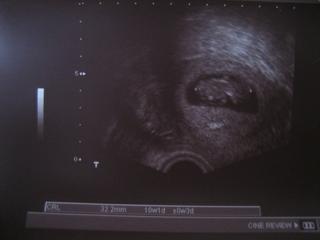

@lintea no to je boziiii.. pekna fotecka 🙂 hlavne se drzte 🙂 ja budu testit zitra..uz ted bojim bojim 🙂